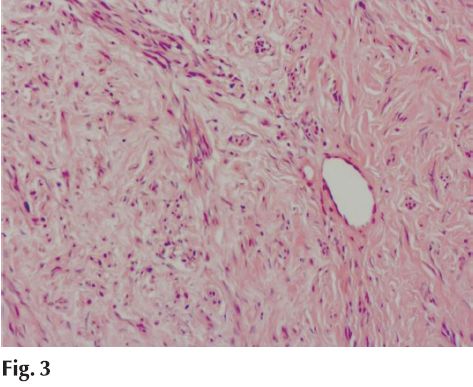

Con el diagnóstico clínico de hiperplasia fibrosa reactiva se realiza biopsia incisional. Histopatológicamente correspondió a una lesión fibromatosa benigna, de histogénesis odontogénica (fig. 3).

En la pieza de resección quirúrgica bajo la mucosa pavimentosa crece una proliferación fibromatosa fusocelular sin atipías que asocia frecuentes islotes de epitelio odontogénico inactivo sin calcificaciones, que orienta a un fibroma odontogénico periférico (fig. 4).